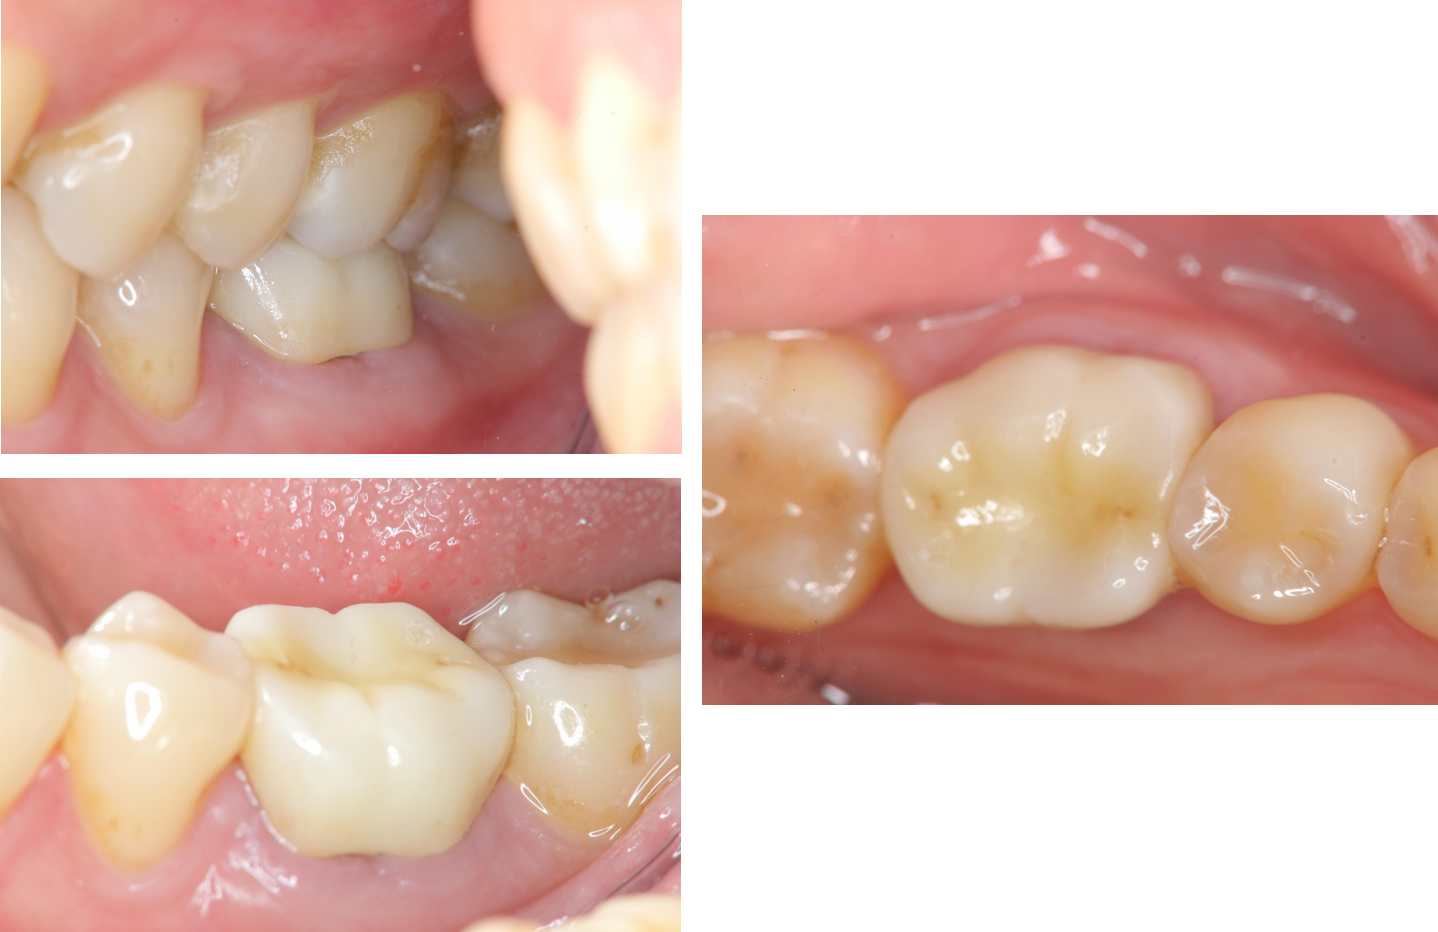

治療前,假牙脫落

臨床照相比色

治療後,口內適應良好

牙齒邊緣密合度良好